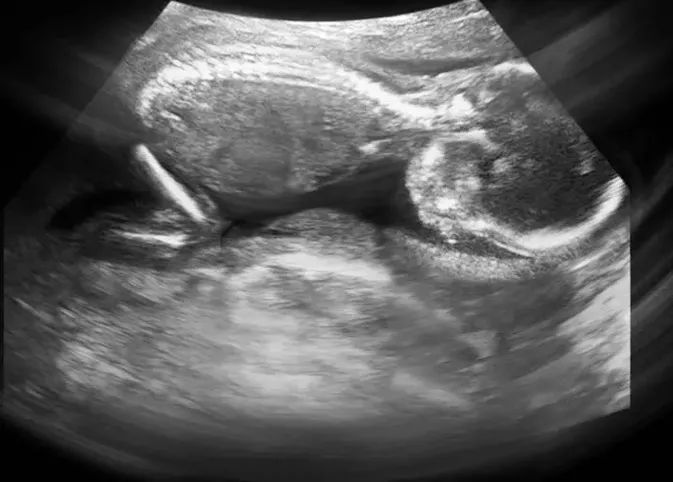

7.FH-胎头

轮廓完整为正常,缺损、变形为异常,脑中线无移位和无脑积水为正常。

8.BDP-胎头双顶径

10.FL-股骨长度

即胎儿大腿骨的长度,又称为“大腿骨长、股骨长”。指胎儿大腿根部到膝部间股骨的长度。它的正常值与相应的怀孕月份的BPD值差2-3厘米左右,比如BPD为9.3厘米,股骨长度应为7.3厘米;BPD为8.9厘米,股骨长度应为6.9厘米等。一般在妊娠20周左右,通过测量FL来检查胎儿的发育状况。

11.SP-脊椎

孕12周后可见胎儿脊柱,孕20周则清晰可辨。胎儿脊柱连续为正常,缺损为异常,可能脊柱有畸形。